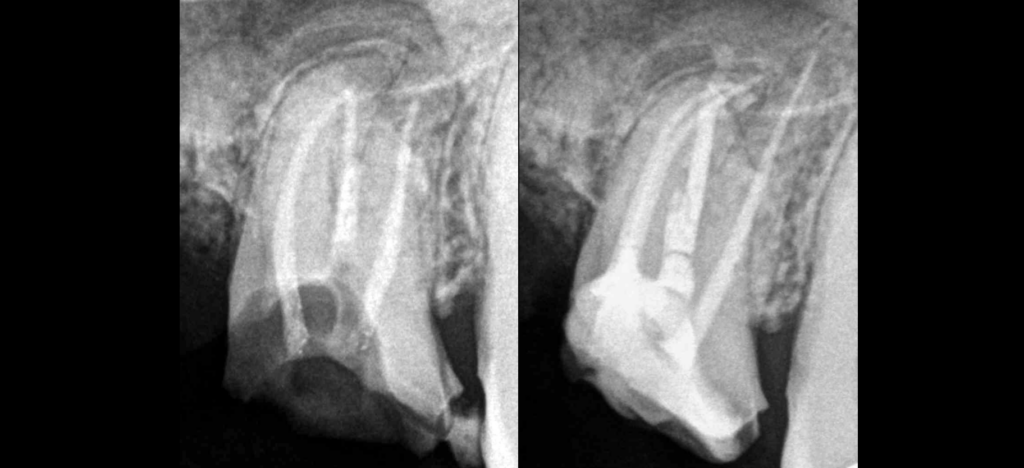

🔍 Pulpe précédemment traitée, os péri apical normal

Projet prothétique

📢 𝐓𝐨𝐮𝐣𝐨𝐮𝐫𝐬 𝐮𝐧 𝐜𝐡𝐚𝐥𝐥𝐞𝐧𝐠𝐞 𝐝𝐞 𝐫𝐞𝐭𝐫𝐚𝐢𝐭𝐞𝐫 𝐥𝐞𝐬 𝐜𝐚𝐧𝐚𝐮𝐱 𝐜𝐨𝐮𝐫𝐛𝐞𝐬 !

➡️ Désobturation au gates 1 dans la portion droite du canal

Puis limes manuelles : avec alternance 15 courte, 10 courte, 8 courte